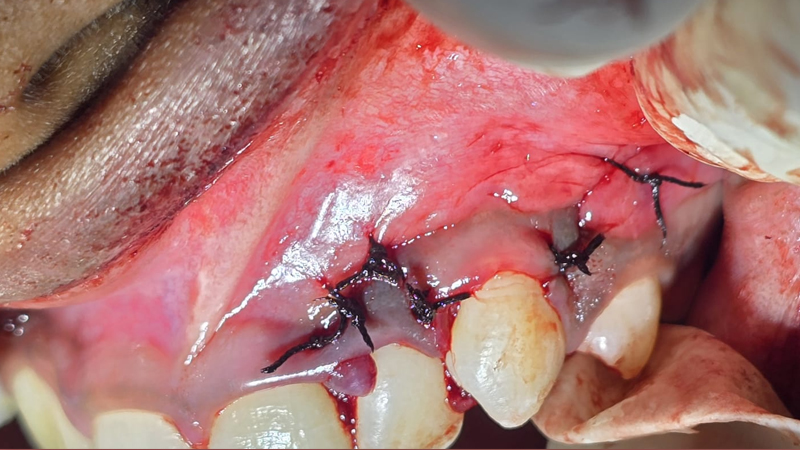

Minor oral surgery may involve procedures such as removal of small cysts, frenectomy, biopsy, extraction of broken or decayed teeth, treatment of infections, and exposure of impacted teeth. Each treatment is carried out by an experienced Oral & Maxillofacial Surgeon who uses advanced techniques and strict sterilization protocols to ensure a safe, comfortable experience.